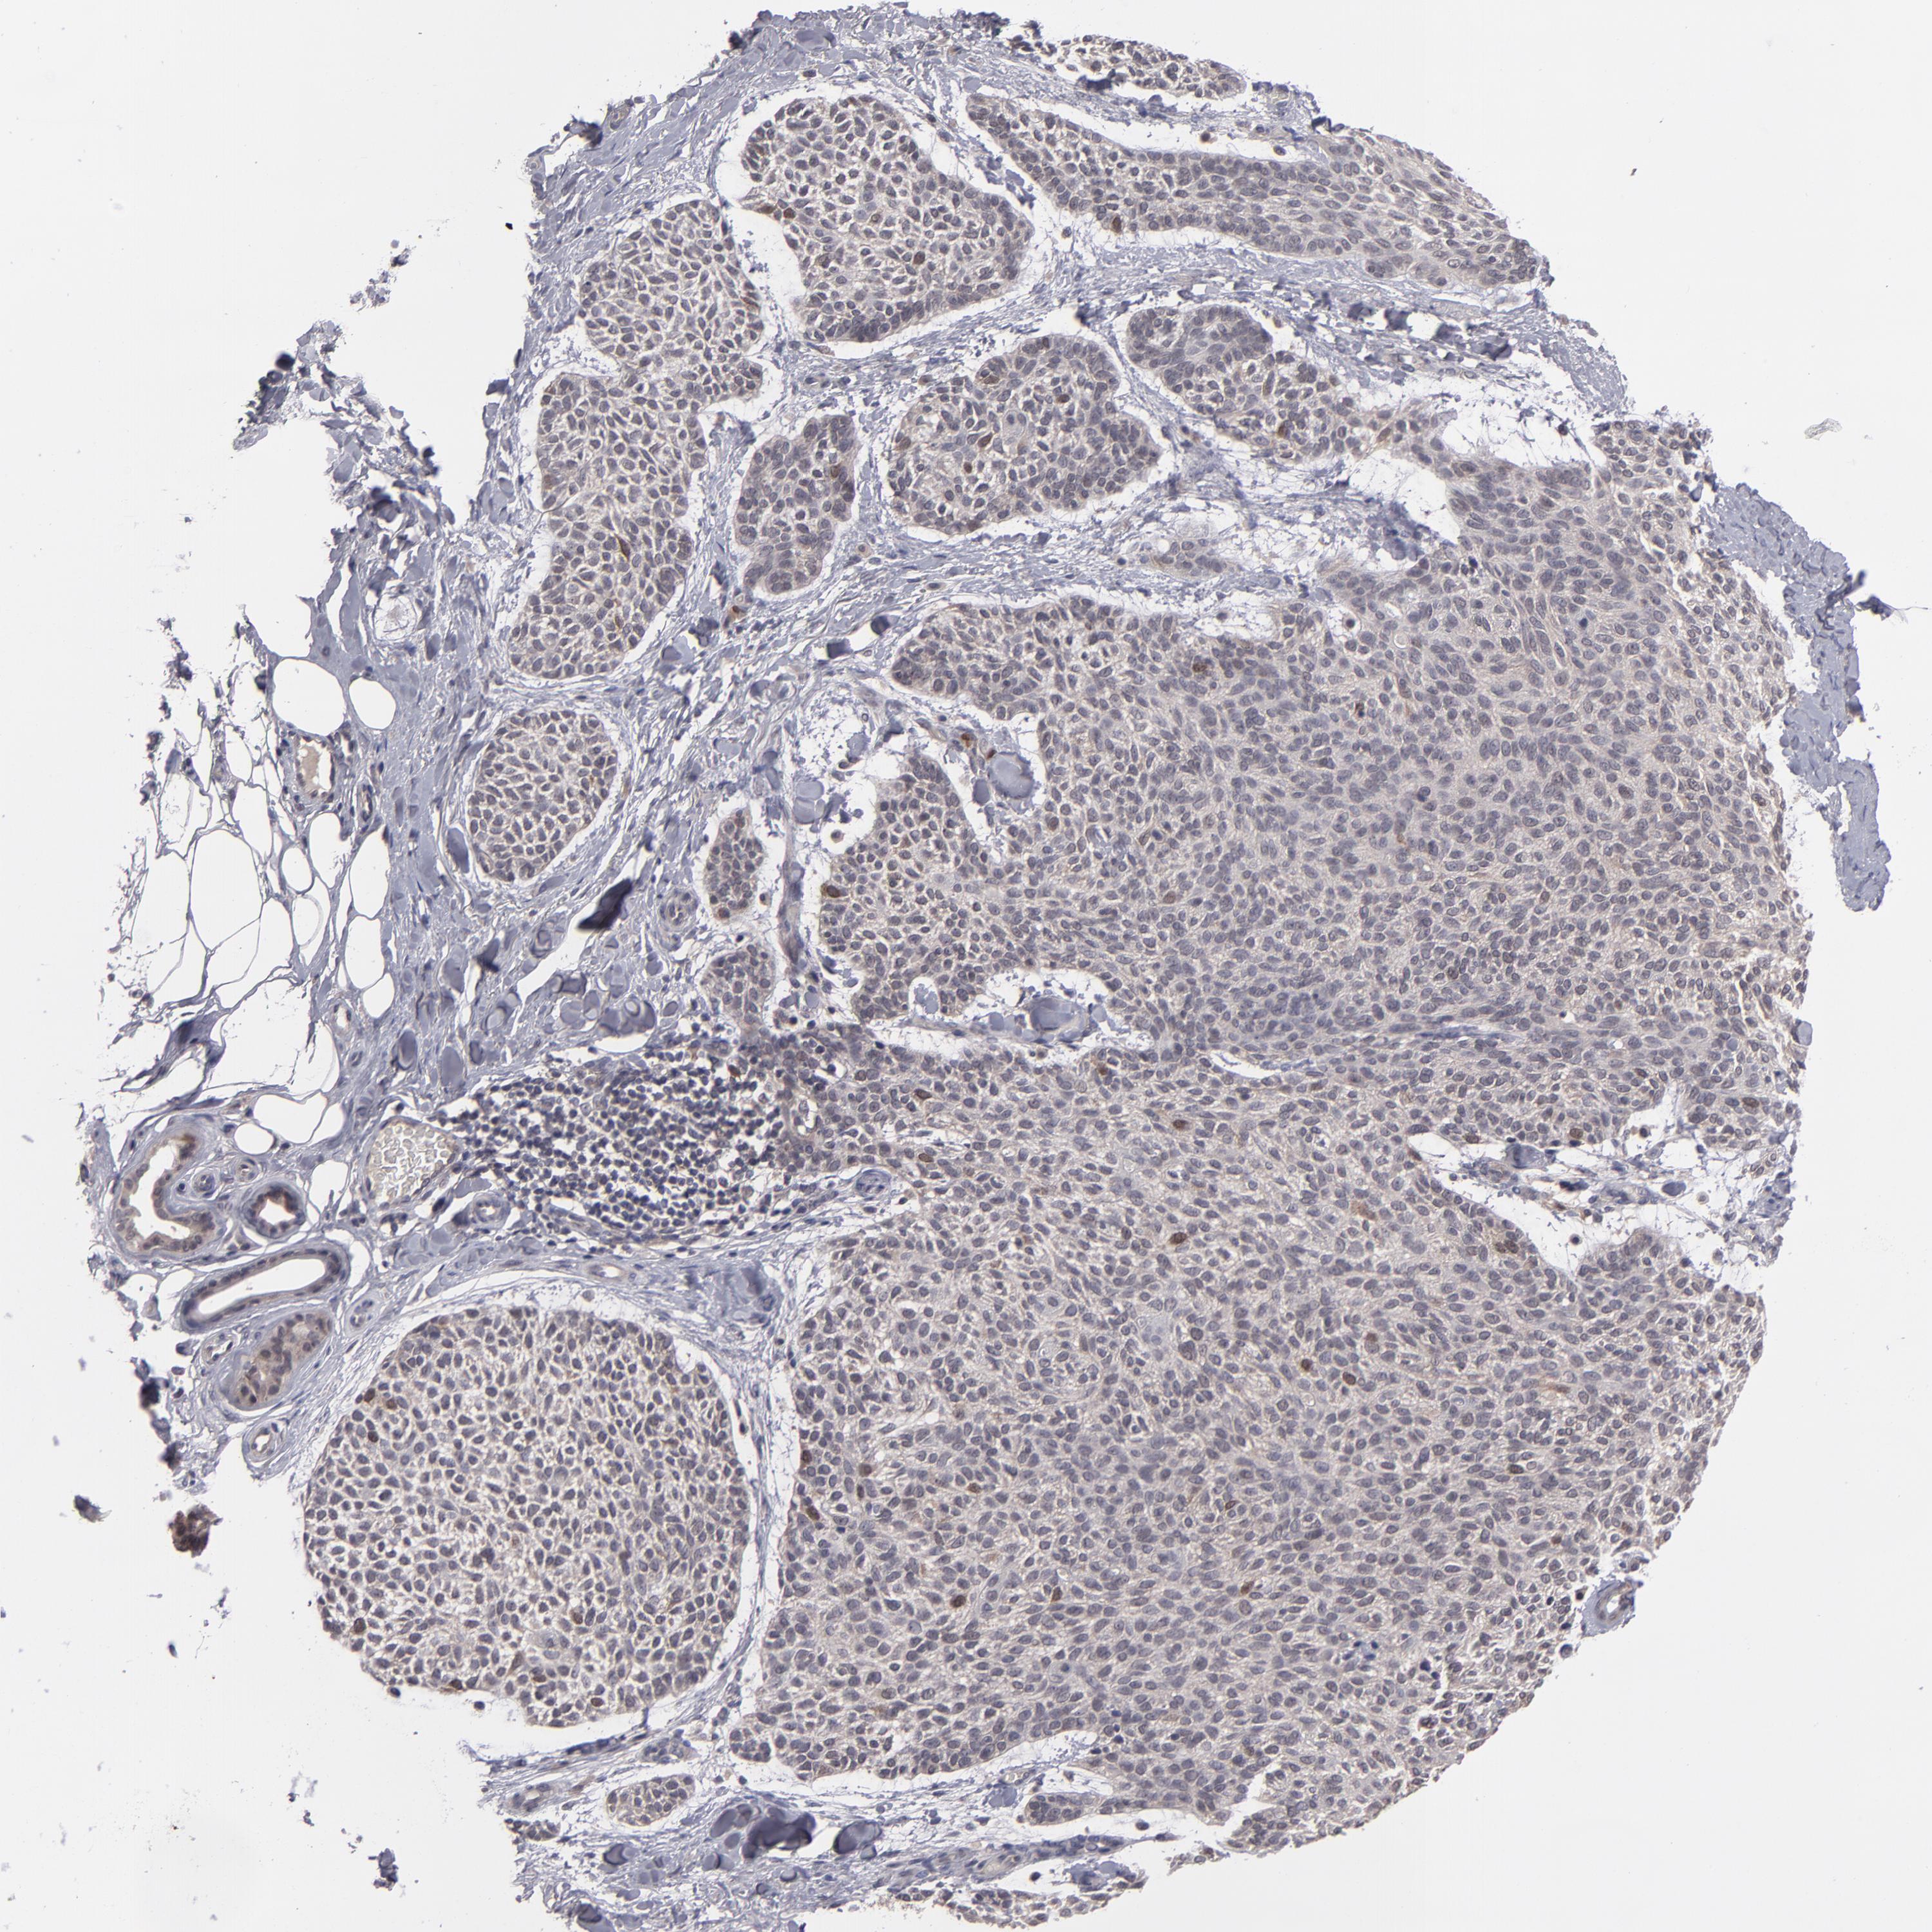

SKIN CANCER - Protein expressioni

A mouse-over function shows sample information and annotation data. Click on an image to view it in a full screen mode. Samples can be filtered based on level of antibody staining by selecting one or several of the following categories: high, medium, low and not detected. The assay and annotation is described here.

Antibody stainingi

Antibody staining in the annotated cell types in the current human tissue is reported as not detected, low, medium, or high, based on conventional immunohistochemistry profiling in selected tissues. This score is based on the combination of the staining intensity and fraction of stained cells.

Each image is clickable and will lead to virtual microscopy that enables deeper exploration of all samples and also displays staining intensity scores, fraction scores and subcellular localization as well as patient and tissue information for each sample.

Antibody HPA074922

Antibody CAB002784

Basal cell carcinoma

Squamous cell carcinoma, NOS